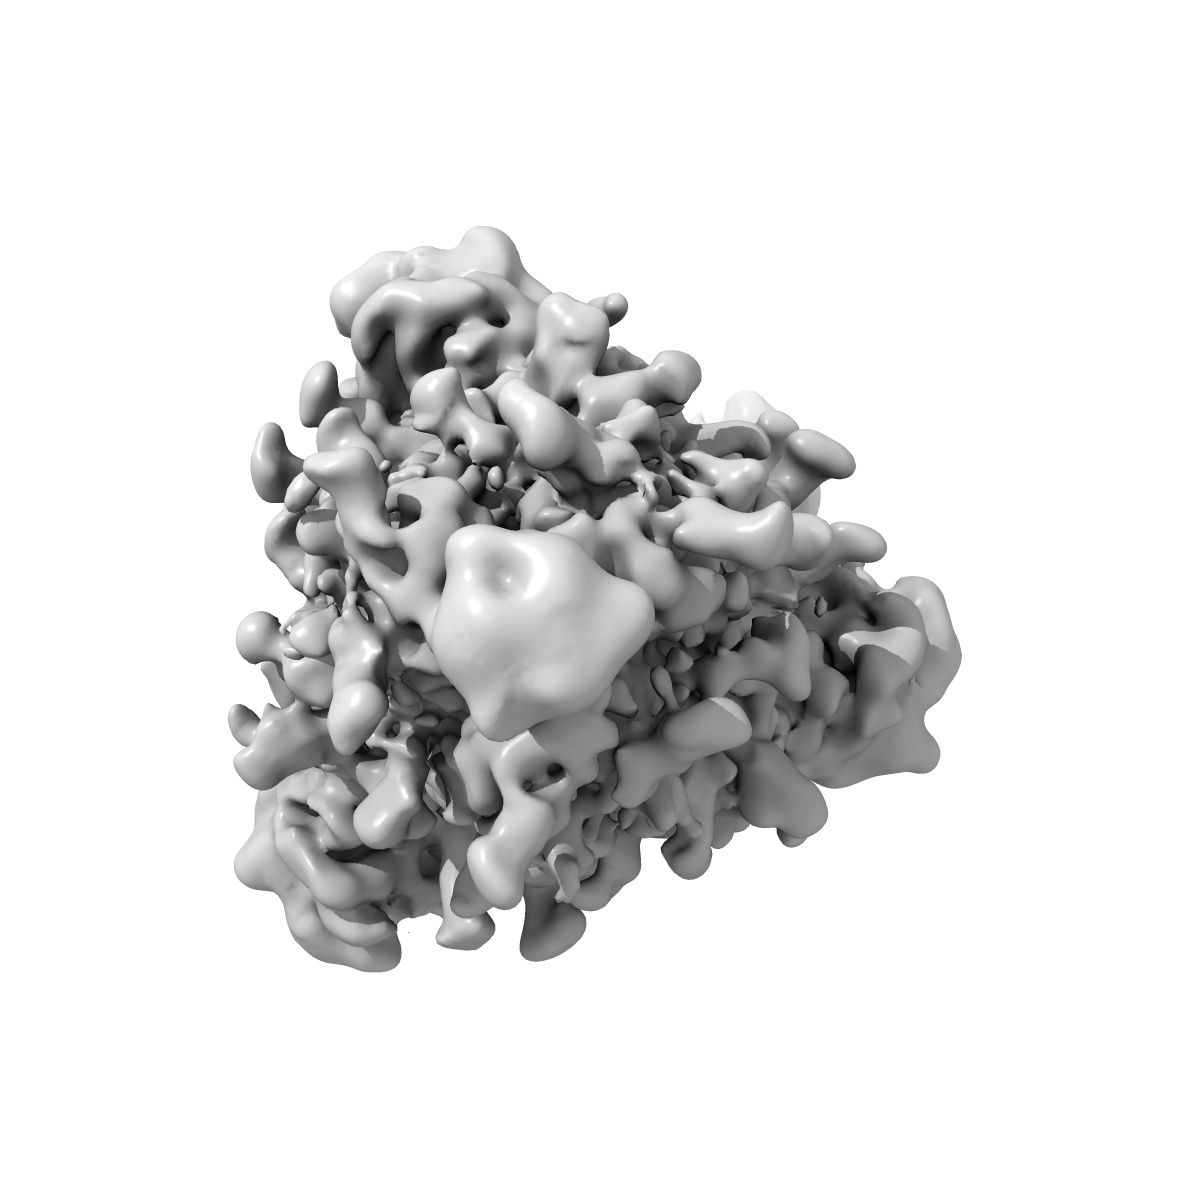

Beta-26 fab in complex with SARS-CoV-2 beta-Spike glycoprotein

Single-particle4.0 Å

Sample: Beta-26 fab in complex with SARS-CoV-2 beta-Spike glycoprotein